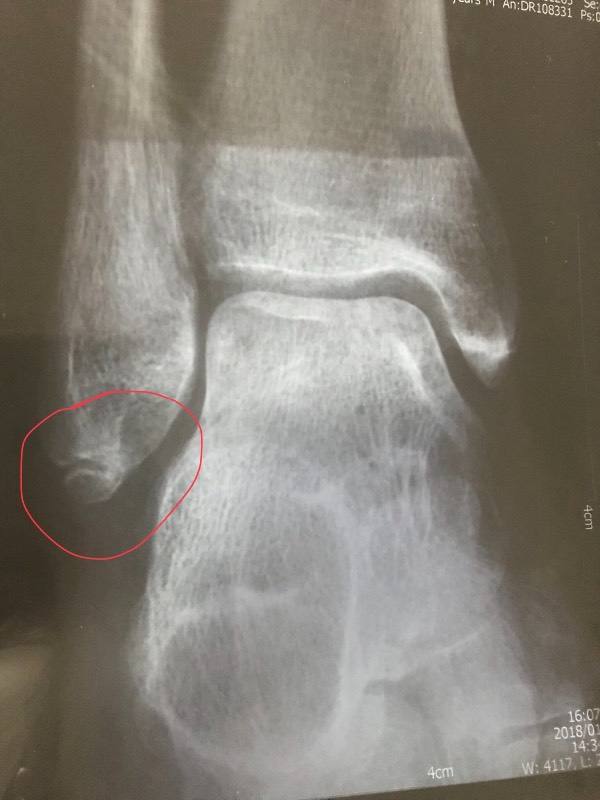

热议 腓骨骨折竟然也有不愈合之时 这个患者究竟该如何处理呢 新闻 蛋蛋赞

脚踝骨折 腓骨末端 撕脱性 知乎